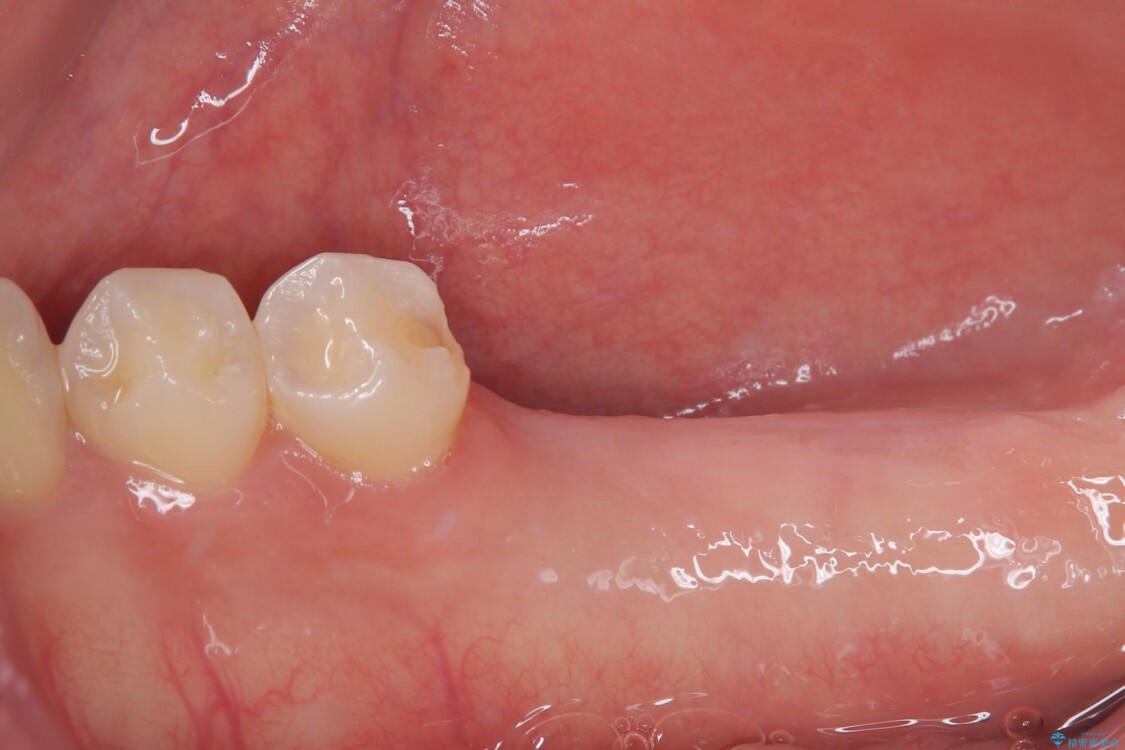

「1年前に抜歯した右下の奥歯にインプラントを入れたい」とのことで来院されました。

インプラント希望部位は右下第一大臼歯と第二大臼歯です。

しかし、噛み合わせの相手である右上の第二大臼歯が、長期間噛み合う歯がなかった影響で**挺出(歯が下に伸びてくる状態)してしまっており、このままではインプラントを埋入して被せもの(上部構造)を入れるためのスペースが不足している状態でした。

治療前

• 挺出歯を圧下してスペースを確保!目立たない部分矯正で下顎大臼歯にインプラント治療を実現 治療前画像